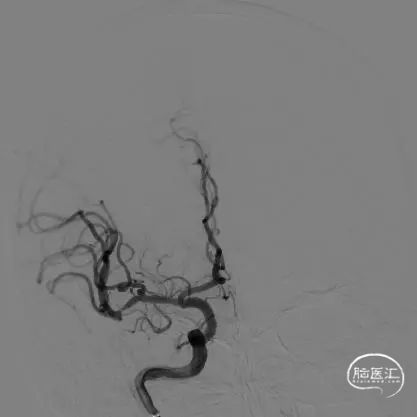

DSA结果:右侧大脑中动脉分叉部动脉瘤,大小约:2.2mmx1.7mm、瘤颈:约2.6mm,未破裂型。

术前影像